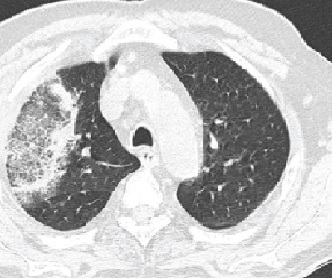

Paciente de 56 anos, submetido a transplante alogênico de medula óssea (TMO) há 45 dias, doador aparentado (irmão 52 anos, hígido), 9/10 (mismatch em DR), comparece ao hospital de referência que o transplantou com quadro de febre persistente de início há cinco dias, com temperatura axilar aferida de 38ºC e hemoptise. Quando questionado, refere tosse produtiva e dor torácica com característica pleurítica. O paciente em questão foi submetido ao TMO após segunda remissão completa de leucemia mieloide aguda, FLT3 positivo na recaída. O esquema de primeira linha utilizado foi o clássico ‘7 + 3’ (Citarabina + Daunorrubicina), enquanto o regime de salvamento foi IDAFLAG + Midostaurina. Como intercorrências durante o tratamento até este momento, o paciente apresentou neutropenia febril com foco em cateter de Hickmann e colite do neutropênico com tratamento eficaz através de antibioticoterapia. Quando recebeu alta do hospital, há 35 dias, não estava mais neutropênico porém manteve uso de ciclosporina como prevenção de doença enxerto-hospedeiro (GVHD). Não estava em uso de antimicrobianos ou antifúngicos profiláticos. Juntamente ao quadro pulmonar, o paciente referia diarreias aquosas em dez episódios ao dia com relato de muco, tendo sido feito o diagnóstico de GVHD agudo intestinal. Solicitado então tomografia de tórax com a imagem abaixo.

Qual o nome do sinal radiográfico observado e qual a suspeita diagnóstica?

BSinal do halo invertido e infecção fúngica por fungo filamentoso